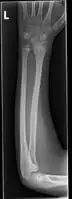

Side view of displaced fractured radius and ulna at wrist